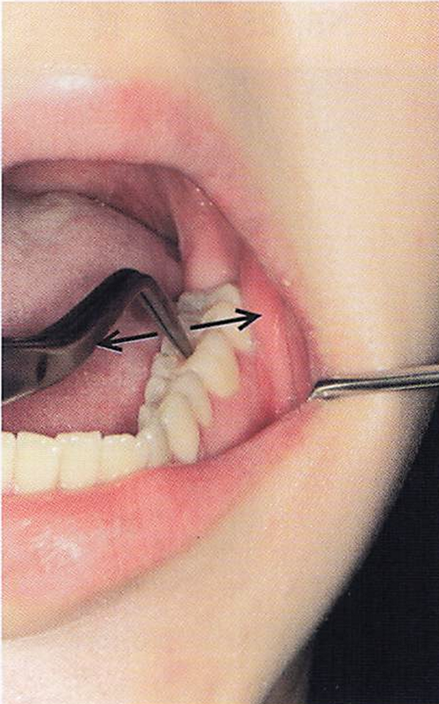

午前-69

歯周組織検査中の写真を別に示す。

矢印で示す方向にのみ0. 5mmの動揺が確認された。

Millerの分類で正しいのはどれか。1つ選べ。

a.0度

b.1度

c.2度

d.3度

解答を見る

b